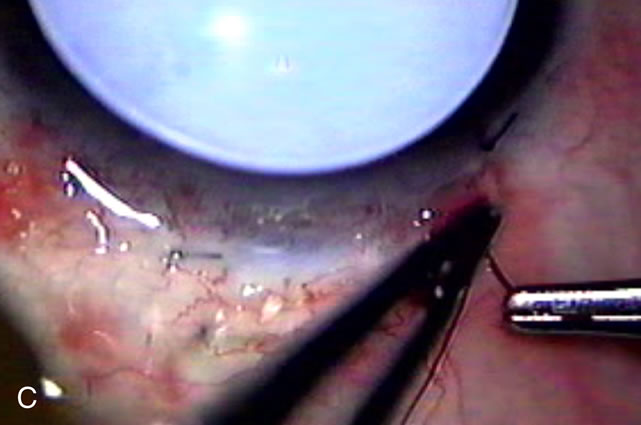

In years past, patients with both cataract and glaucoma frequently provided overwhelming surgical challenges for the ophthalmologist. The ability to carry out phacoemulsification through a 3.2-mm corneal incision along with inserting a foldable IOL is a vast improvement over 11-mm incisions that were common a decade ago (Fig. 1). The anatomical and inflammatory changes to the eye are less with small incision techniques, improving the likelihood of success with concomitant glaucoma surgery. Pharmacologic inhibition of fibrosis along with postoperative wound revision increases the long-term success rate of filtration surgery when combined with lens extraction. (Fig. 2). The learning curve may be steep at times, but the blending of cataract and glaucoma surgical skills slowly falls into place as the surgeon constantly learns and upgrades his or her technique.

Fig. 1. The anatomic advantage of small incision cataract surgery for the glaucoma patient. A. Long-term bleb function with a large cataract incision is difficult to achieve with either ECCE-trabeculectomy or trabeculectomy followed later by ECCE. This bleb failed to form sufficiently when combined with large incision ECCE. The inflammation, bleeding, and long-term wound healing with stimulation of fibroblasts associated with this technique are more likely to cause bleb failure. In addition, the increased iris manipulation necessary to deliver the nucleus and subsequent iris repair adds to the long-term breakdown of the blood aqueous barrier. B and C. Two-site phacotrabeculectomy has the advantage of small incision cataract surgery combined with separate site trabeculectomy. The incision size is one third the size of the standard ECCE. The inflammation is less severe, and cataract wound healing is confined to the temporal area. Visual rehabilitation with phacoemulsification and foldable IOL is much faster. Phacoemulsification allows successful lens extraction even in the unfriendly environment of a smaller pupil compared with ECCE. The trabeculectomy is performed in an entirely different site, well away from the wound healing associated with temporal phacoemulsification. The likelihood of this filter functioning long-term is greater than with ECCE-trabeculectomy. D. The surgeon also has the option of single-site phacotrabeculectomy with foldable IOL. Both the lens extraction and trabeculectomy are performed through one small 3.5-mm limbal incision.